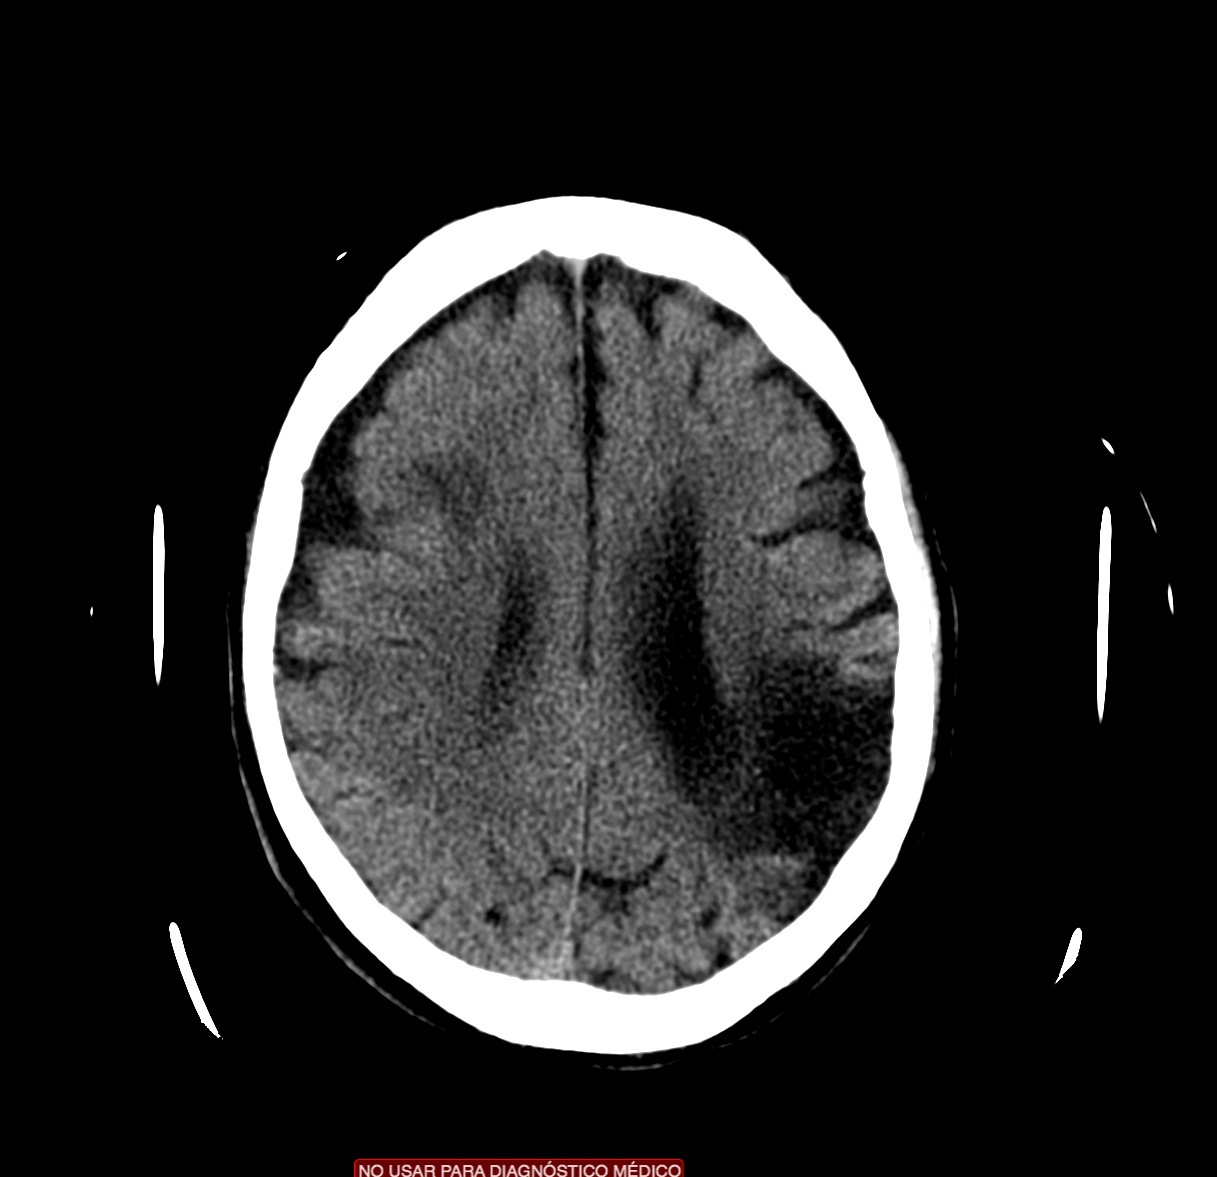

Se investiga un poco más y se descubre que el paciente había acudido diez días antes, también con cierta clínica de debilidad en hemicuerpo izquierdo, y se le realizó un TAC de cráneo. Observemos por tanto el estudio previo:

Pues bien, ante los hallazgos descritos, se clarifica que estamos ante un paciente el cual no tiene una masa y que ha sufrido una lesión isquémica hace diez días. Ahora, sobre dicha lesión, tenemos una imagen con un aumento de densidad que sugiere sangrado por una parte y otra hipodensidad en la perifería que correspondería a un edema. Por tanto, descartamos un sangrado intraparenquimatoso de novo. El paciente tiene más de 65 años, no es hipertenso, la imagen del sangrado no es de alta densidad, lo que se opone a una fase aguda o hiperaguda, y tenemos el TC de cráneo previo donde ya se advertía un proceso de tipo isquémico. Por tanto, nos quedan dos opciones, o estamos ante un resangrado de un ACV o estamos ante una Perfusión de lujo.